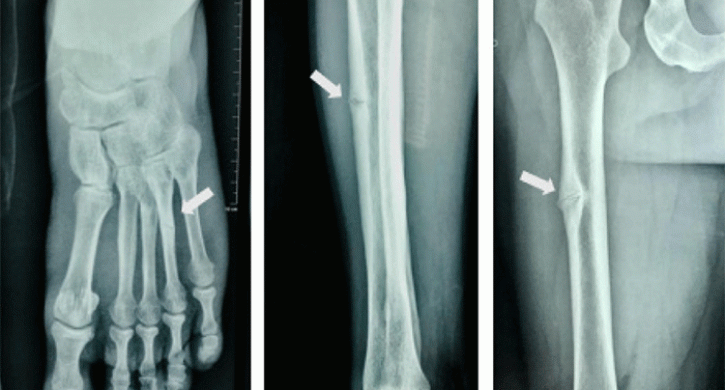

«Из амбулаторной карты я узнала, что несколько лет назад у ребенка обнаружили деформацию стопы. Ортопед предложил операцию, после которой возникли осложнения – остеопороз костей стопы. Потребовалась реабилитация и дополнительное лечение. Назначена терапия специализированными препаратами, на этом фоне развилась почечная недостаточность и девочку в срочном порядке перевели в нефрологическое отделение», – рассказывает врач Алена Побединская.

«Никто не заметил неоднократно выявленного снижения щелочной фосфатазы. Просто продолжали реабилитацию. Снижение ЩФ часто игнорируется специалистами. Это может сигнализировать о возможном наследственном заболевании, гипофосфатазия (ГФФ), которое проявляется множеством проблем: выпадением зубов, частыми переломами, искривлением позвоночника, низким ростом, почечной недостаточностью, снижением памяти, задержкой речевого развития», – говорится генетик Побединская .